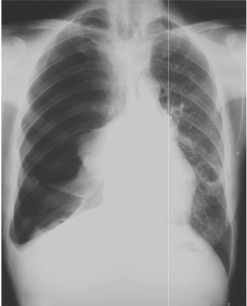

- Paciente de 26 años de edad, que ingresó a nuestro Servicio tras sufrir un accidente de moto. En el ingreso se encontraba hemodinámicamente inestable, con una presión arterial de 107/54 mmHg, frecuencia cardíaca de 106 por min, un puntaje de Glasgow de 15, saturación de O2 de 89%, taquipnéico, dolor intenso en tórax y nauseas. Se obtuvo la siguiente imagen radiológica:

- Indique según la imagen que piensa que le está ocurriendo al paciente.

- Además de la RX tórax ¿realizaría alguna prueba Dx más?

- Qué tratamiento administraría al paciente.

- Esa TA y el aumento de la FC de qué le haría sospechar.